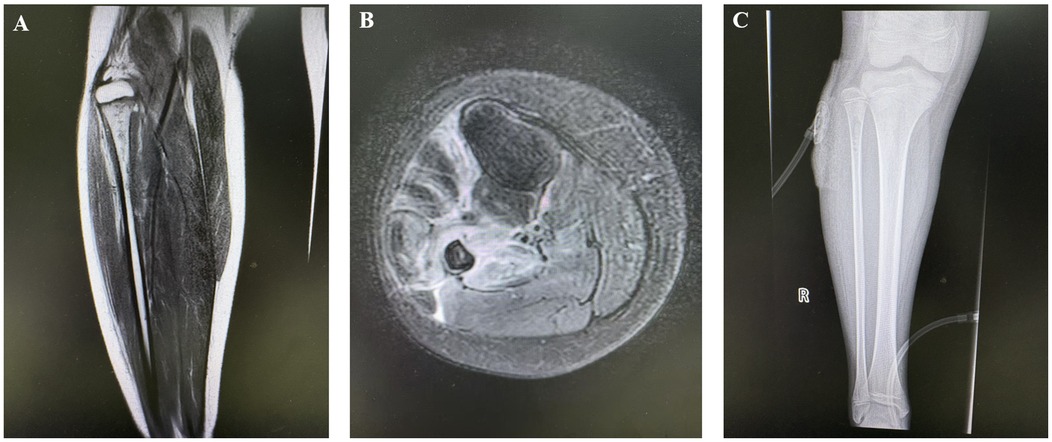

Abstract Objective To summarize and analyze the clinical characteristics, diagnosis, treatment, and prognosis of pediatric fibular osteomyelitis, and to analyze related influencing factors, providing evidence for clinical management of pediatric osteomyelitis in rare locations. Methods A retrospective analysis was conducted on the clinical data of pediatric patients with fibular osteomyelitis from January 2018 to December 2024, including demographic characteristics, clinical manifestations, laboratory and imaging examinations, microbiological results, treatment modalities, and follow-up outcomes. Results A total of 13 patients were included (9 males, 4 females) with a median age of onset of 7.3 years. There were 11 acute cases and 2 chronic cases. The main clinical manifestations were bone pain, fever, and local abscess formation. The positive rate of microbiological culture was 76.9%, with Staphylococcus aureus being the most common pathogen (including 1 case of MRSA). Two patients responded effectively to antibiotic therapy alone, while 11 cases required surgical intervention, including fibular fenestration, debridement, segmental resection, and VSD therapy. All patients showed significant reduction in inflammatory markers after treatment. During 3-24 months of follow-up, 3 cases experienced recurrence requiring repeat surgery, with no severe disability or deformity observed. Conclusion Pediatric fibular osteomyelitis has an insidious onset and poses diagnostic challenges. Staphylococcus aureus, particularly MRSA, represents the primary pathogen, with higher rates of surgical intervention and recurrence compared to other long bones. Early accurate diagnosis, adequate antibiotic therapy, and individualized surgical intervention are crucial for improving prognosis.